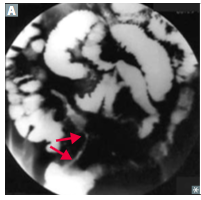

demonstrates the gross findings with Crohn’s disease. T

The middle portion of bowel seen here has a thickened wall and the mucosa has lost the regular folds. The serosal surface demonstrates reddish indurated adipose tissue that creeps over the surface.

Serosal inflammation leads to adhesions. The areas of inflammation tend to be discontinuous throughout the bowel

Chrohn: String sign on barrium swollow

creeping fat, bowel wall thickening (“string sign” on barium swallow x-ray A ), linear ulcers, fissures.